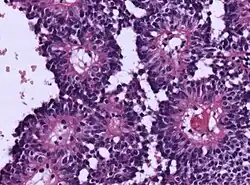

Micrograph of an astroblastoma showing the characteristic nuclear pervivascular pseudorosette. H&E stain.

• Radial arrangement as a pseudorosette